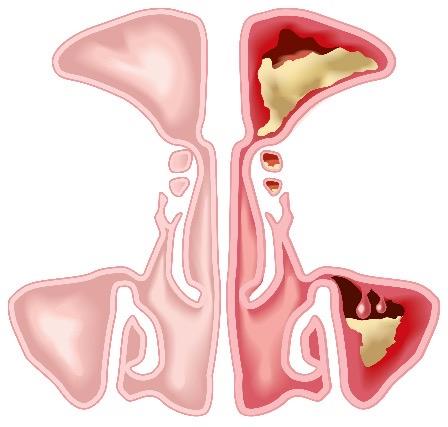

Common Clinical Presentation EGPA

>90% of patients with EGPA have asthma that arises in adulthood, rarely shows seasonal exacerbations, and worsens over time.

ENT symptoms, such as CRSwNP, are common and polyps commonly recur after surgical excision.

The diagnosis of EGPA should be considered in patients with asthma, CRSwNP, and eosinophilia.

CRSwNP, chronic rhinosinusitis with nasal polyps; ENT, ears, nose and throat. Emmi G, et al. Nat Rev Rheumatol. 2023;19(6):378-393.